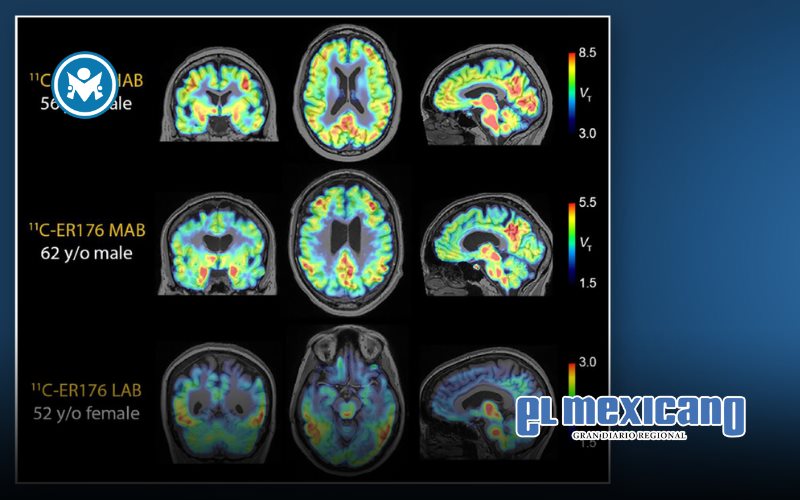

La especificidad anatómica de los marcadores de inflamación en los estudios PET (por sus siglas en inglés) es crucial, ya que las enfermedades que causan demencia afectan distintas regiones del cerebro.

El liderazgo del Hospital Houston Methodist en esta área queda de manifiesto en el desarrollo innovador de tecnología de imagen PET, en particular con el uso del nuevo trazador PET 11C-ER176.

A diferencia de otros trazadores PET, el 11C-ER176 permite observar la inflamación de forma eficaz en todos los tipos genéticos de pacientes.

Este trazador actúa sobre la proteína TSPO, un marcador de inflamación, lo que permite a los científicos obtener imágenes detalladas incluso en personas que antes no podían ser evaluadas debido a su perfil genético.

Gracias a este equipo, los investigadores pueden diferenciar con claridad qué estructuras del cerebro están afectadas por inflamación y cuáles contienen proteínas anormales. Esta distinción no podía hacerse en estudios anteriores, incluso en algunos considerados fundamentales, debido a la menor resolución de las imágenes.